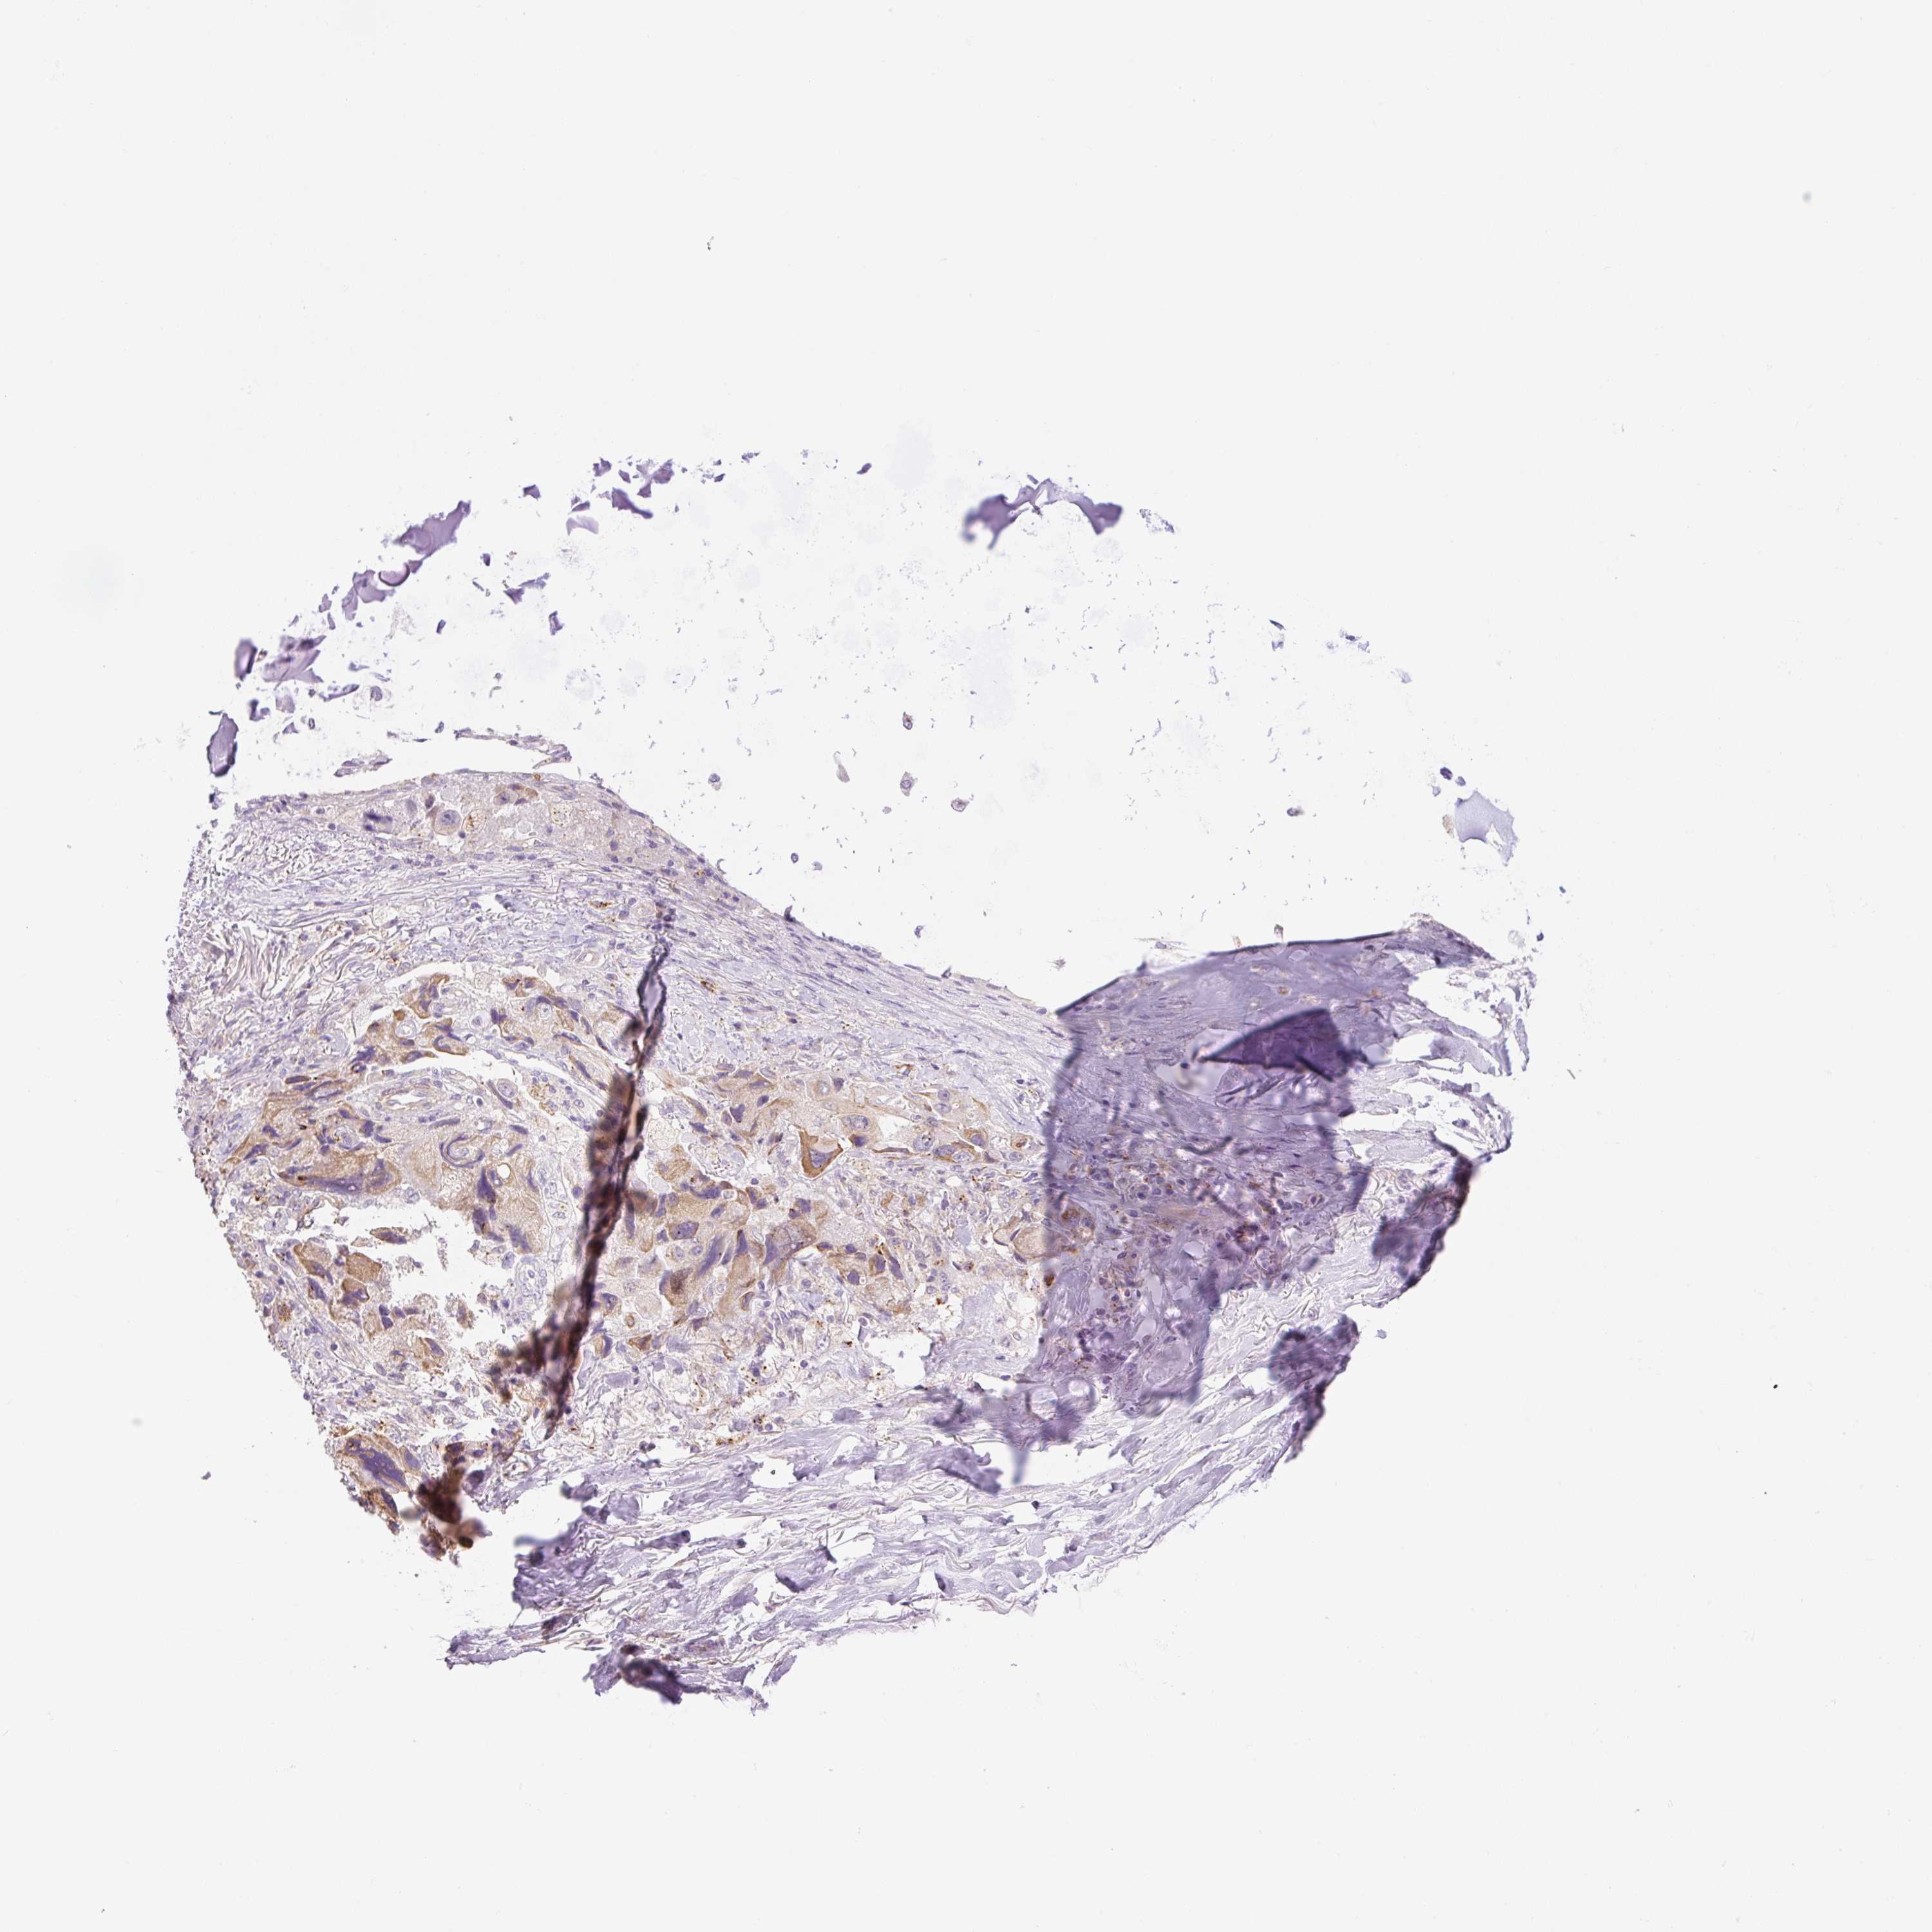

CANCER LUNG CANCER Show tissue menu

Lung cancer

Human cancer

TCGA RNA samplesi

RNA-seq data is reported as average FPKM (number Fragments Per Kilobase of exon per Million reads), generated by the The Cancer Genome Atlas (TCGA) .

Normal distribution across the dataset is visualized with box plots, shown as median and 25th and 75th percentiles. Points are displayed as outliers if they are above or below 1.5 times the interquartile range. FPKM values of the individual samples are presented next to the box plot.

Average pTPM 0.1

Number of samples 497